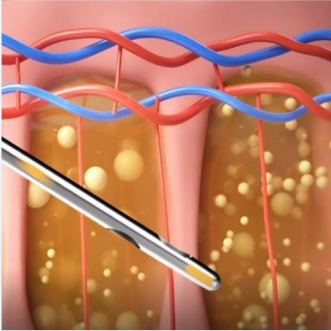

심부볼은 볼 안쪽 깊숙이 위치한 지방 덩어리로

피하지방과는 달리 다이어트로는 빠지지 않는 고유한 구조물입니다.

볼 안쪽 깊은 곳에 위치

다이어트로 빠지지 않는 지방

입안을 절개하여 외부 흉터 없이

심부볼 지방을 안전하게 제거합니다.